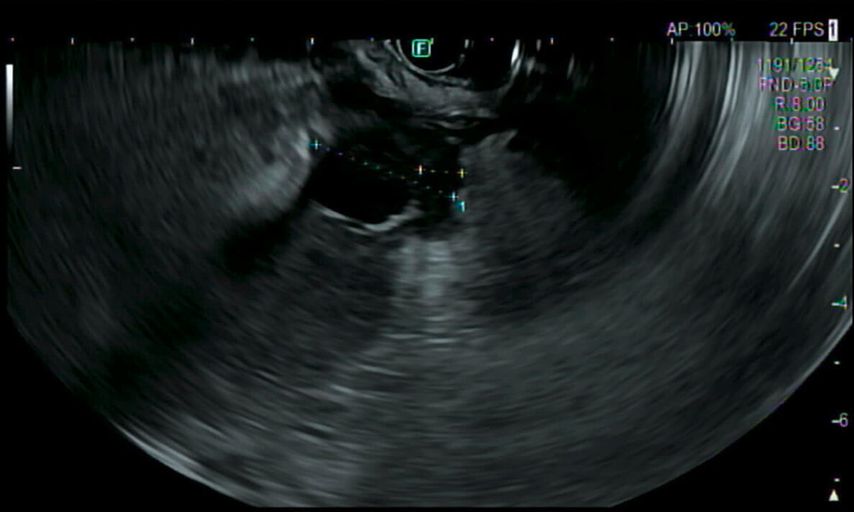

Es folgen eine sonografisch gezielte Punktion und perkutane Pigtail-Drainageanlage in die Fluidokollektion (Abb.3). Prompt entleeren sich 2,8l Pus. Die Drainage wird regelmäßig gespült und für 10 Tage belassen. In der Kultur des Punktats können Streptococcus anginosus und Klebsiella pneumoniae nachgewiesen werden, die initial eingeleitete Antibiose mit Piperacillin/Tazobactam wird antibiogrammgerecht umgestellt. Eine Kontrollgastroskopie (Abb.4) zeigt einen unauffälligen Befund am Pylorus und im Bulbus sowie in der Pars descendens duodeni, zahlreiche Biopsien der Magenschleimhaut ergeben eine geringgradige chronische, inaktive Corpusgastritis mit mukosalem Ödem.